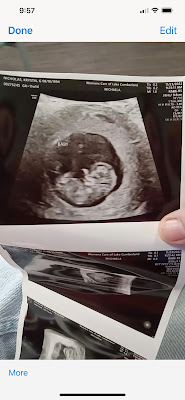

Here are ultrasound pictures of my great-grandson. Yes, he's a boy, but every great once in a while they do make a mistake and the baby turns out to be of the opposite sex. Either a boy or a girl would be just fine with me.

I can't wait to meet my new great-grandson!